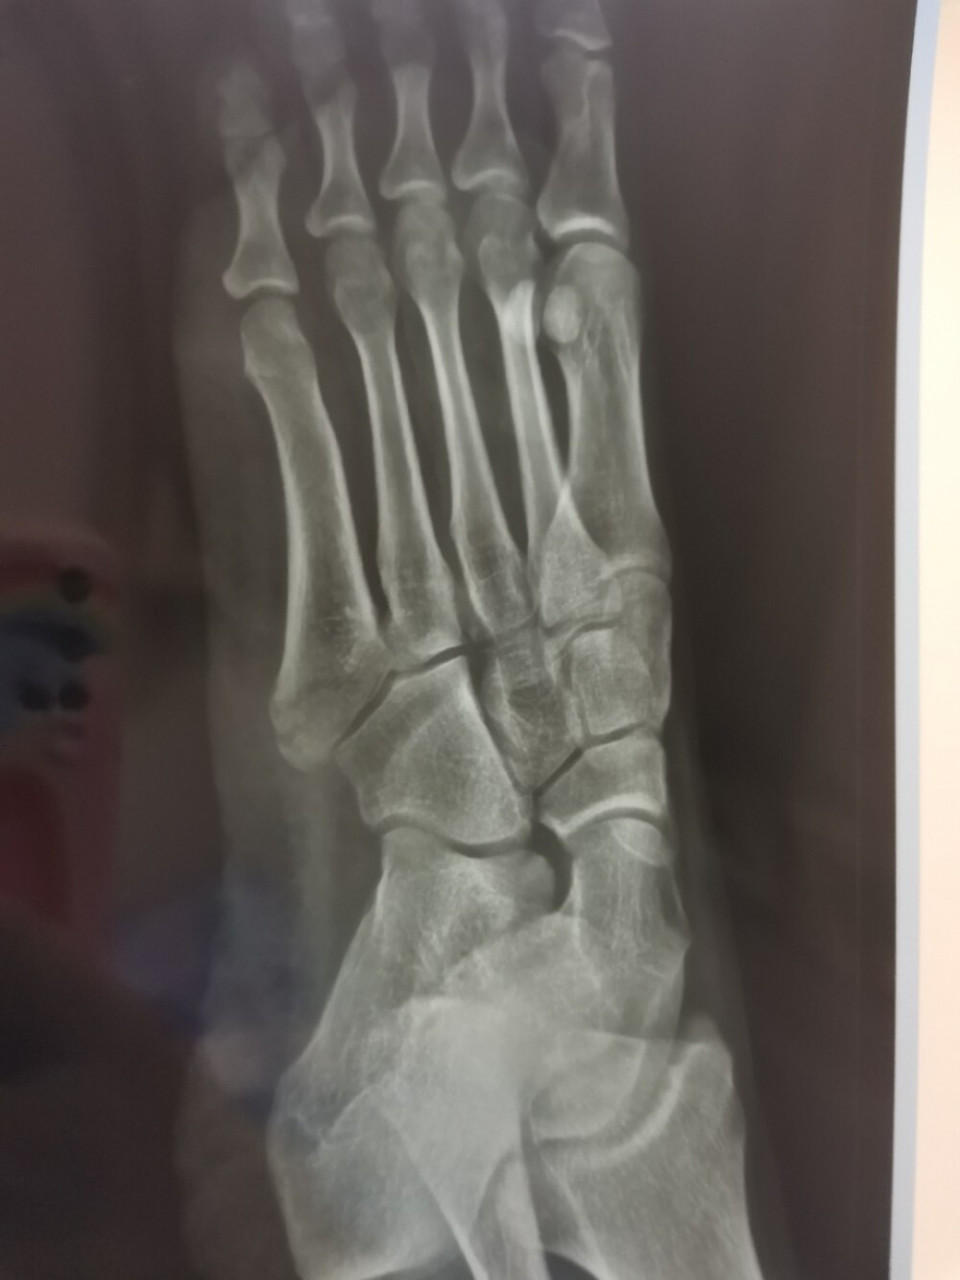

左脚第5跖骨基底部骨折,慢慢康复路

记录下足部第五跖骨基底部骨折陆续更新

第五跖骨基底部骨折25天,石膏第19天 最近几天脚疼的厉害,今天去复查

22的片子,感觉快一个月了骨折线还是一模一样一点没愈合.

左足舟骨骨折已经20天了,医生说起码一个月才能下地,这个片子也看不懂

左脚第5跖骨骨折恢复记录